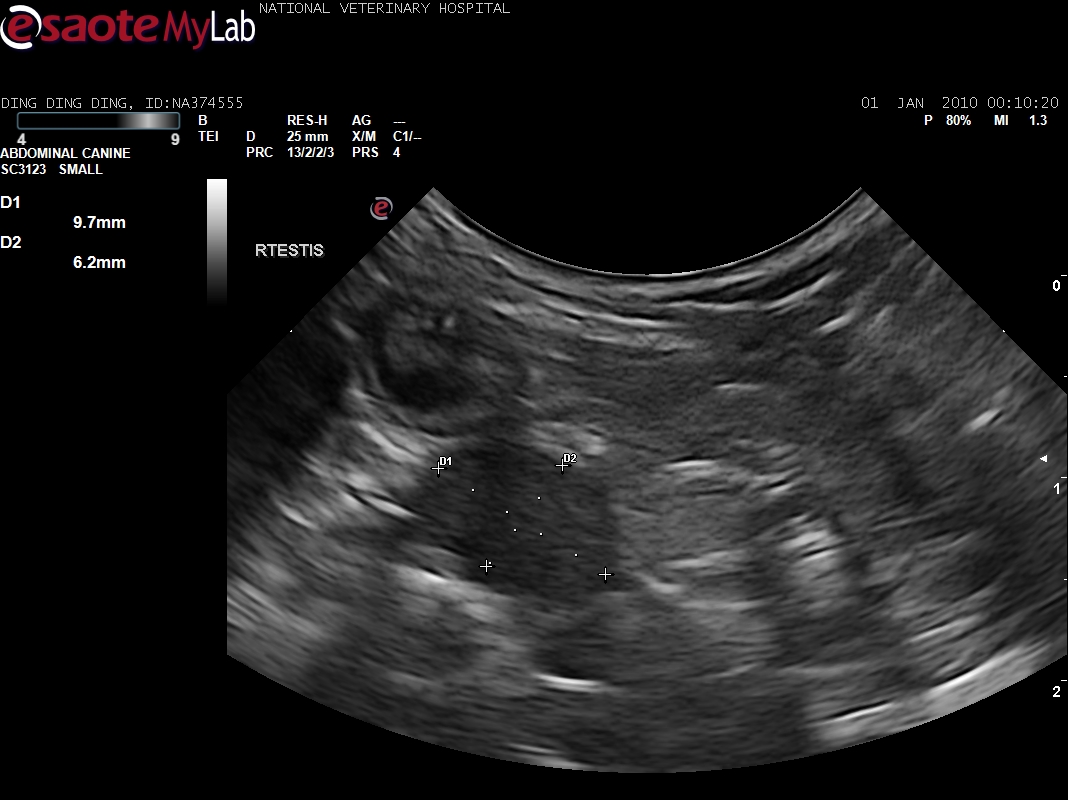

1